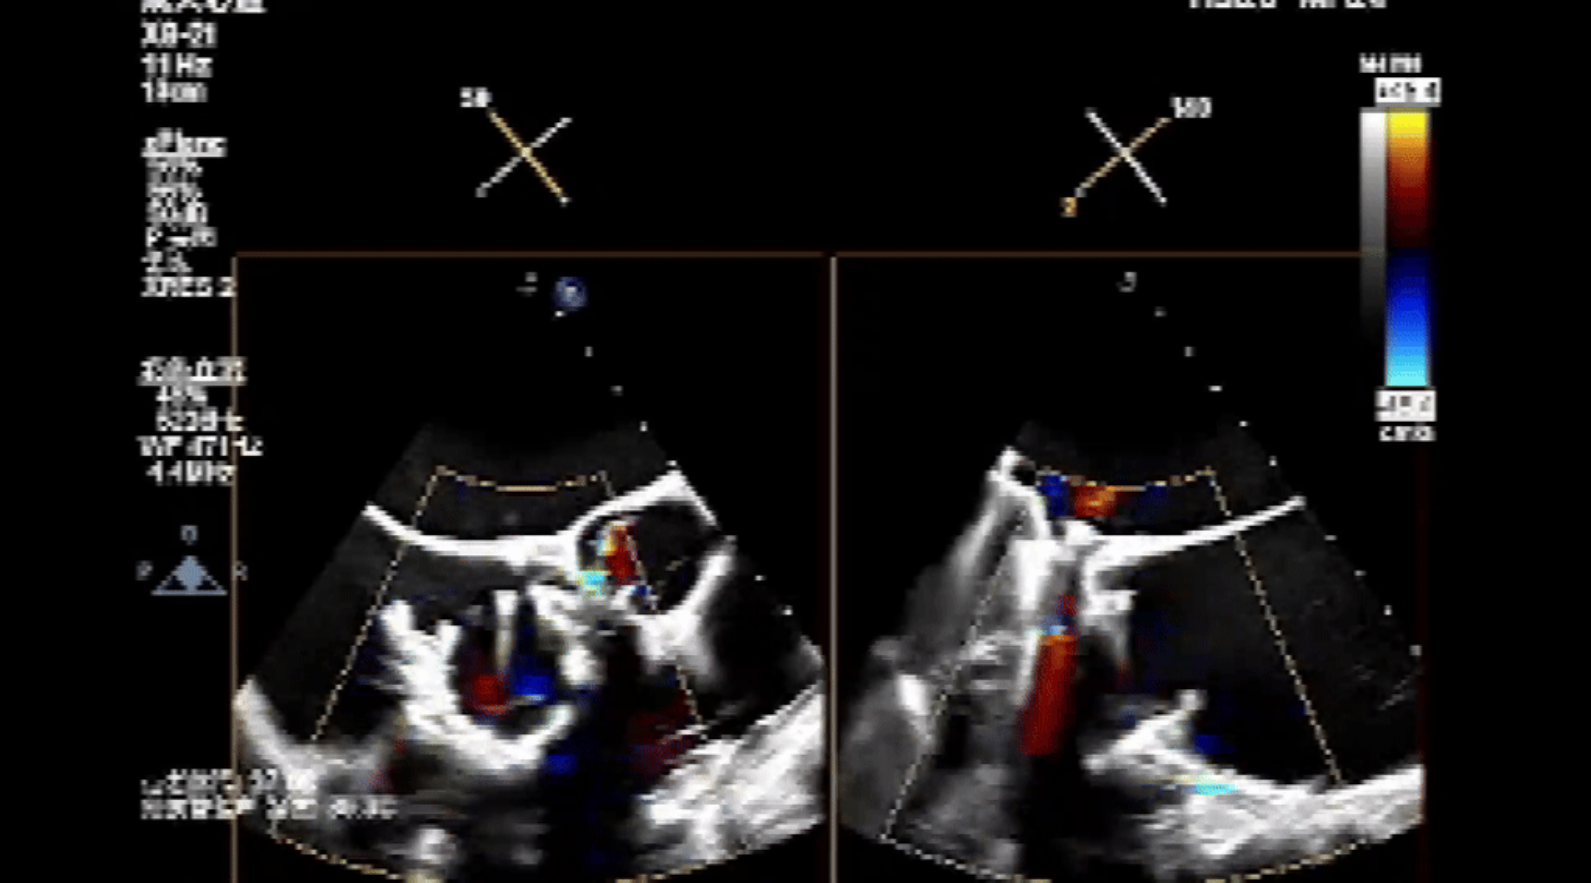

術(shù)前心臟超聲提示:三尖瓣大量返流,右心房容積明顯增大,三尖瓣瓣環(huán)顯著擴(kuò)張。

術(shù)后心臟超聲提示:Lux-Valve Plus植入術(shù)后,三尖瓣瓣環(huán)處可見(jiàn)人工瓣膜回聲,未見(jiàn)返流,人工瓣膜穩(wěn)定,瓣葉開(kāi)閉良好,連續(xù)多普勒估測(cè)三尖瓣平均跨瓣壓差僅為1mmHg。